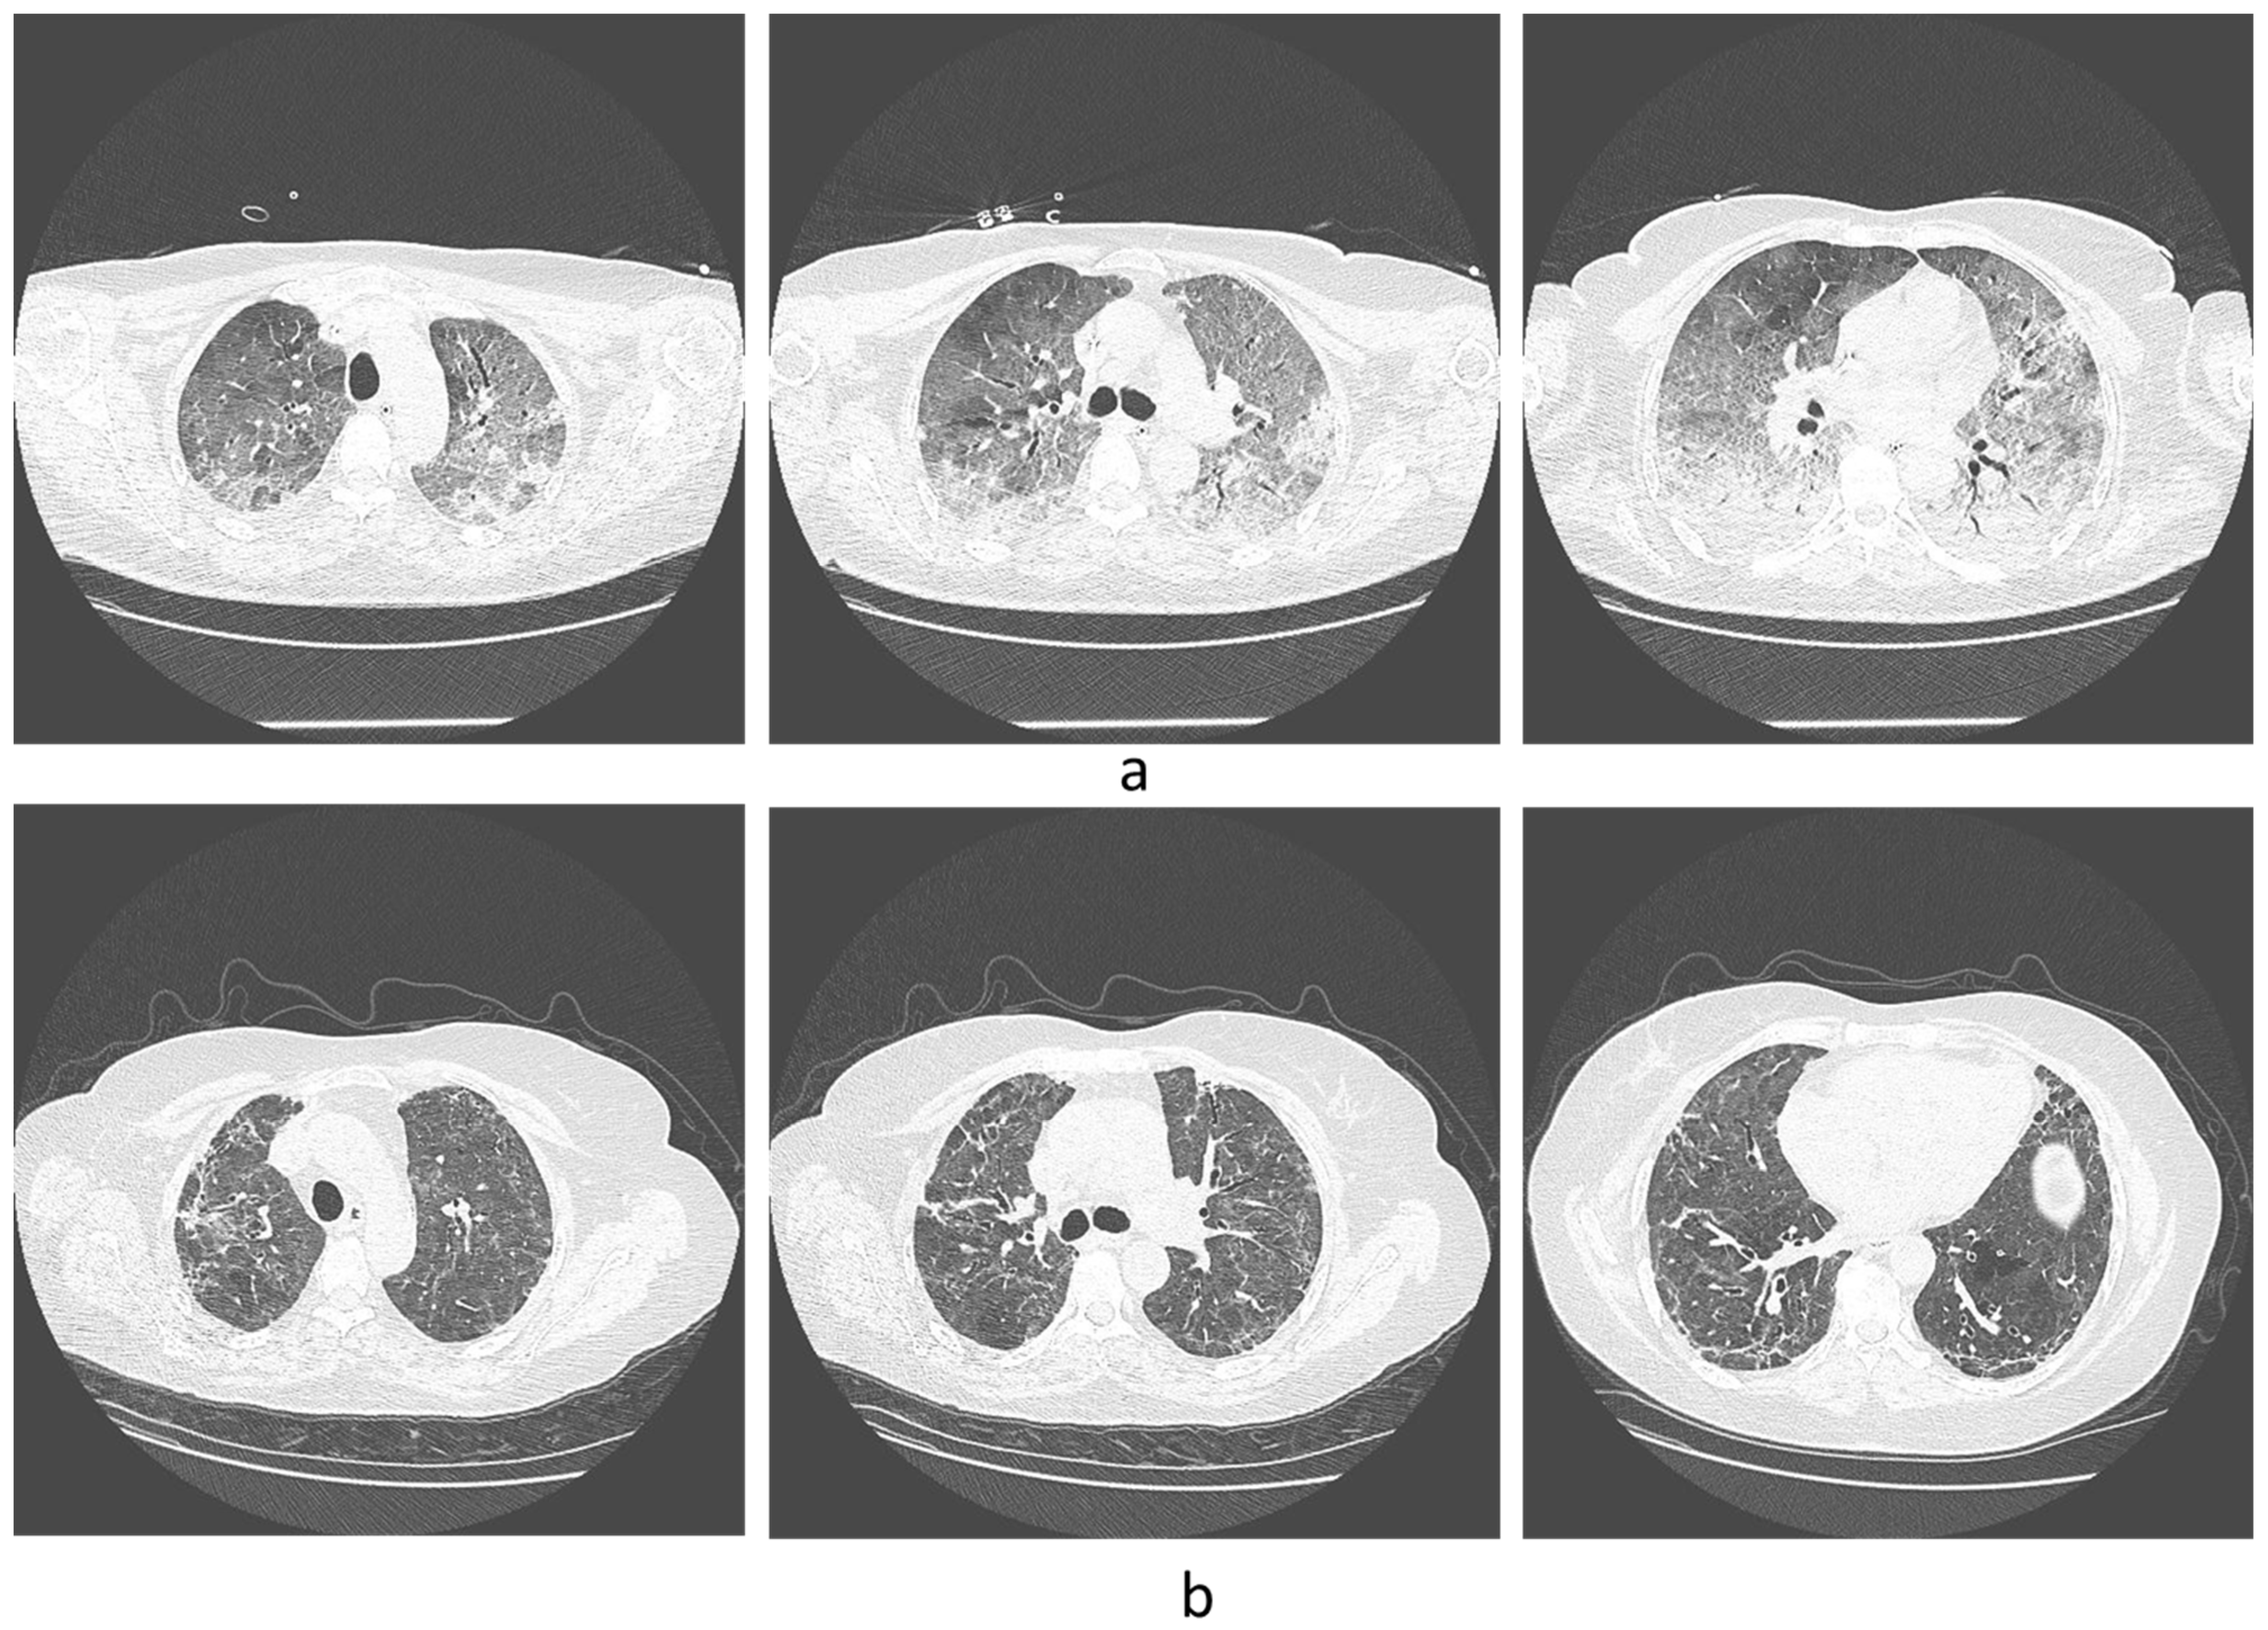

- Mogami, R.; Araújo Filho, R.C.; Chantong, C.; Gianella, C.; Santos de Almeida, F.C.; Baptista Koifman, A.C.; Jauregui, G.F.; Mafort, T.T.; da Silva Bessa da Costa, H.; Peres dos Santos, G.A.; et al. The Importance of Radiological Patterns and Small Airway Disease in Long-Term Follow-Up of Postacute COVID-19: A Preliminary Study. Radiol. Res. Pract. 2022, 2022, 7919033. [Google Scholar] [CrossRef]

- Kotzé, P.B.; Manthey, R.; Griffith-Richards, S.; Ackermann, C.; Klusmann, K. Computed tomography chest findings in post-acute COVID-19 lung disease at a South African regional hospital—A descriptive study. Pan Afr. Med. J. 2023, 44, 175. [Google Scholar] [CrossRef]

- Lehmann, A.; Gysan, M.; Bernitzky, D.; Bal, C.; Prosch, H.; Zehetmayer, S.; Milos, R.-I.; Vonbank, K.; Pohl, W.; Idzko, M. Comparison of pulmonary function test, diffusion capacity, blood gas analysis and CT scan in patients with and without persistent respiratory symptoms following COVID-19. BMC Pulm. Med. 2022, 22, 196. [Google Scholar] [CrossRef]

- Pan, F.; Yang, L.; Liang, B.; Ye, T.; Li, L.; Li, L.; Liu, D.; Wang, J.; Hesketh, R.L.; Zheng, C. Chest CT Patterns from Diagnosis to 1 Year of Follow-up in Patients with COVID-19. Radiology 2022, 302, 709–719. [Google Scholar] [CrossRef]

- Corsi, A.; Caroli, A.; Bonaffini, P.A.; Conti, C.; Arrigoni, A.; Mercanzin, E.; Imeri, G.; Anelli, M.; Balbi, M.; Pace, M. Structural and functional pulmonary assessment in severe COVID-19 survivors at 12 months after discharge. Tomography 2022, 8, 2588–2603. [Google Scholar] [CrossRef]

- Watanabe, A.; So, M.; Iwagami, M.; Fukunaga, K.; Takagi, H.; Kabata, H.; Kuno, T. One-year follow-up CT findings in COVID-19 patients: A systematic review and meta-analysis. Respirology 2022, 27, 605–616. [Google Scholar] [CrossRef]

- Lerum, T.V.; Meltzer, C.; Rodriguez, J.R.; Aaløkken, T.M.; Brønstad, E.; Aarli, B.B.; Aarberg-Lund, K.M.; Durheim, M.T.; Ashraf, H.; Einvik, G.; et al. A prospective study of pulmonary outcomes and chest computed tomography in the first year after COVID-19. ERJ Open Res. 2023, 9, 00575. [Google Scholar] [CrossRef]